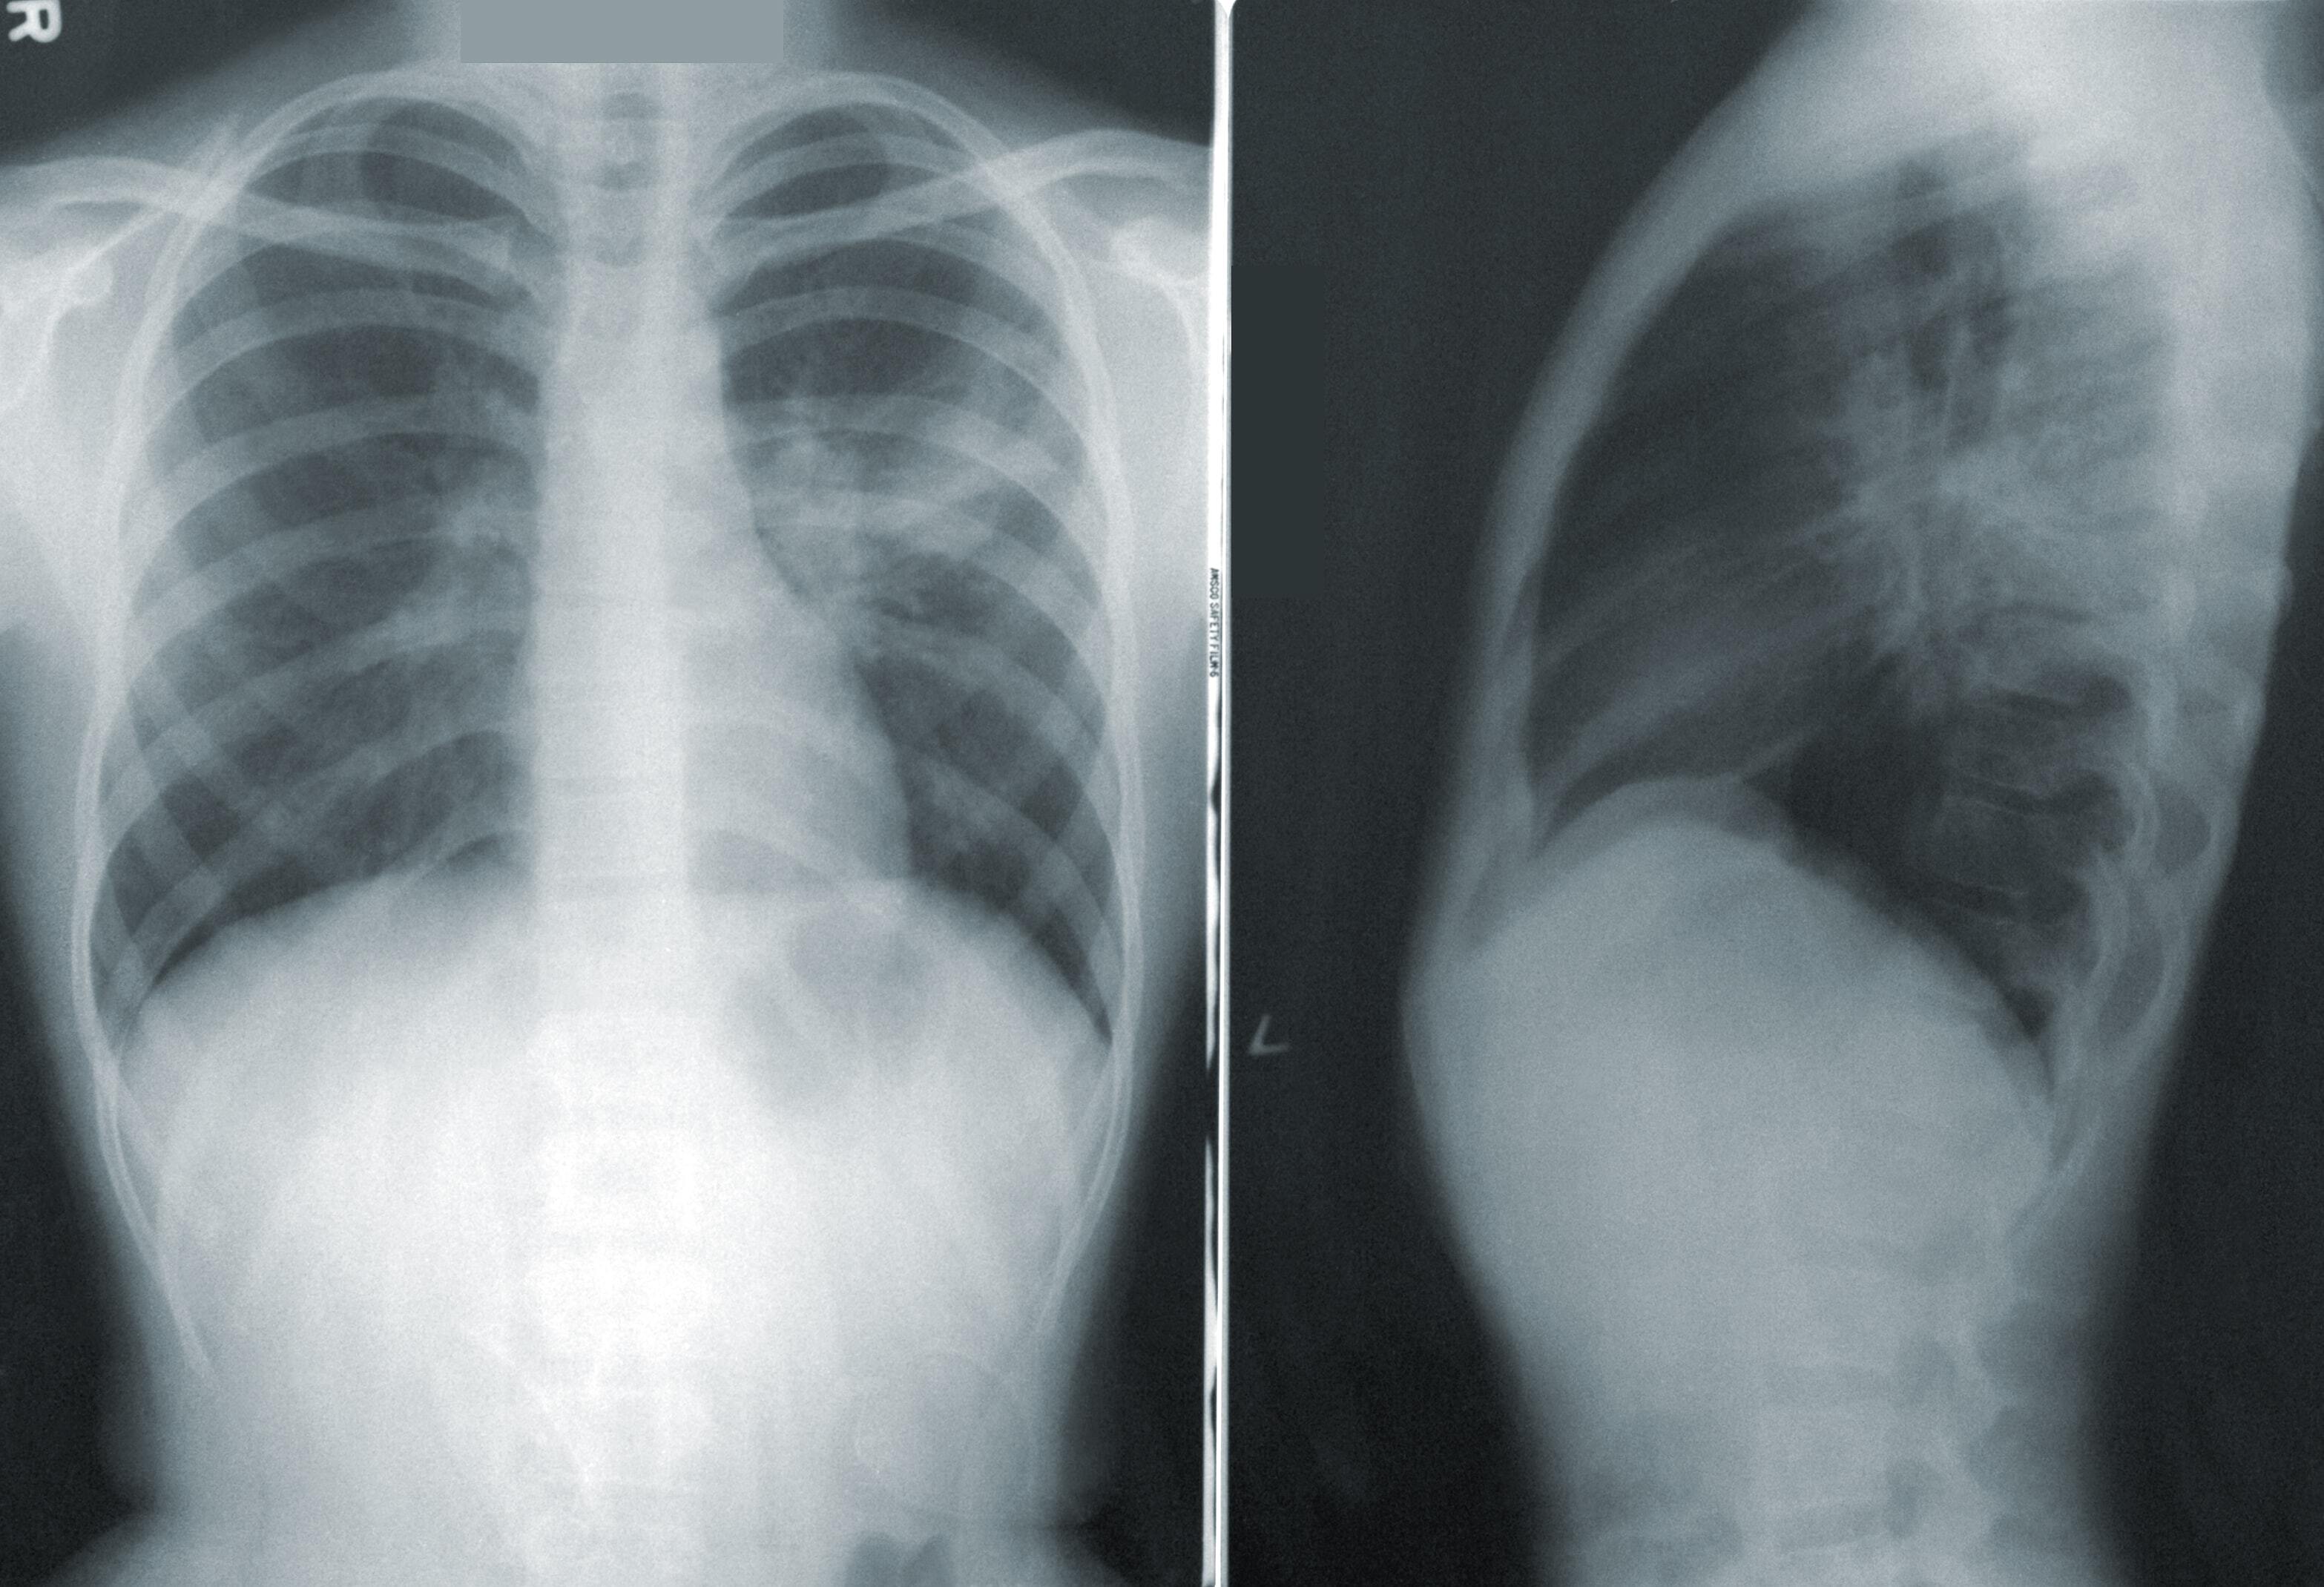

Каким людям нужно проходить обследование на рак лёгких: отвечает врач

Согласно исследованию National Lung Screening Trial («Национальное испытание по скринингу лёгких»), проведённому в США, полезнее всего проходить обследование для выявления рака лёгких на ранних стадиях трём категориям людей. И это не только курильщики. ferra.ru »